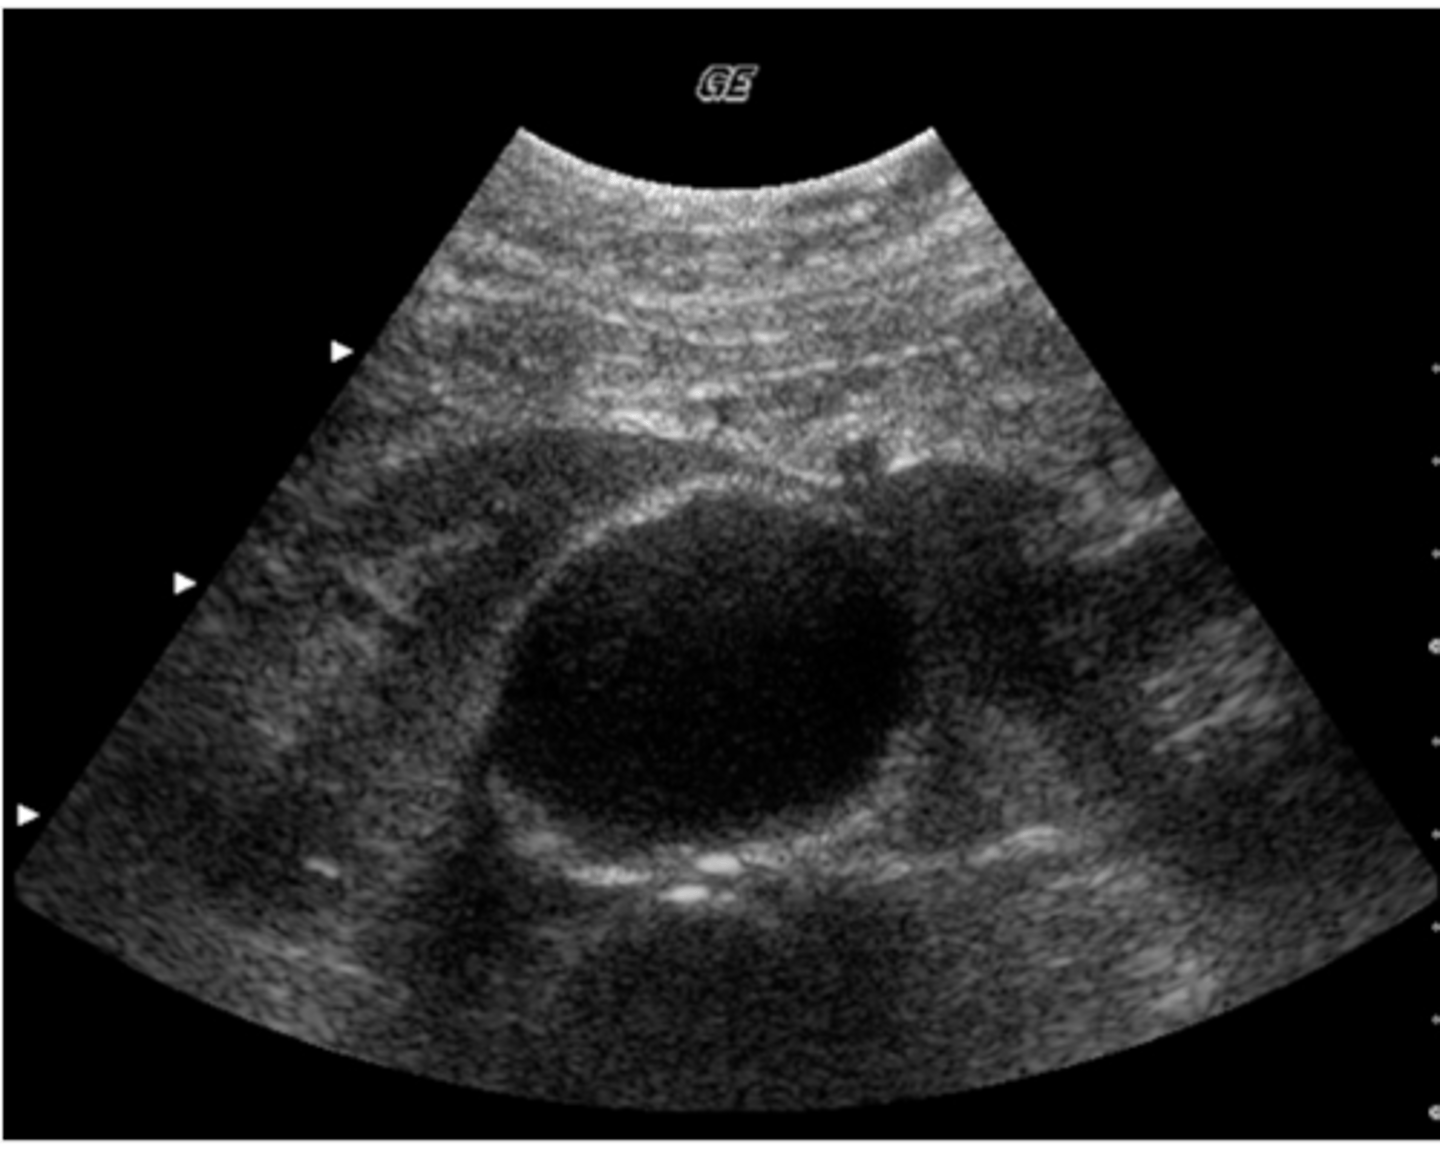

e. splenic cysts

This patient was regerred for an abdominal ultrasound because of epigastric pain and tenderness. This image was obtained from the left upper quadrant. Which of the following describes the ultrasound findings?

a. pleural effusion

b. splenomegaly

c. ascites

d. splenic metastases